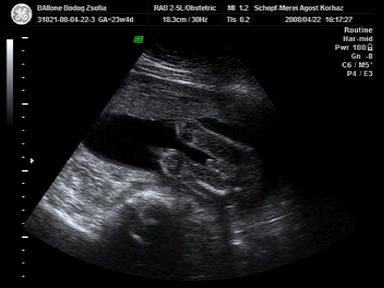

Én 24 hetesen voltam 4D-n és nagyon jól látszott minden. Mindjárt rakok is fel egy képet KisBubbenről.

Egy hete 665 g volt. BPD 5.9 cm (fejátmérő), AC 19.27 cm (haskörfogat), Fejétől a fenekéig 29.55 cm és az FL 4.5 cm (combcsont hossza) Nekem elmondta a doki, aki csinálta az UH-át, hogy mik ezek a "kódok"!

Remélem sikerül a képet beillesztenem...

Kép